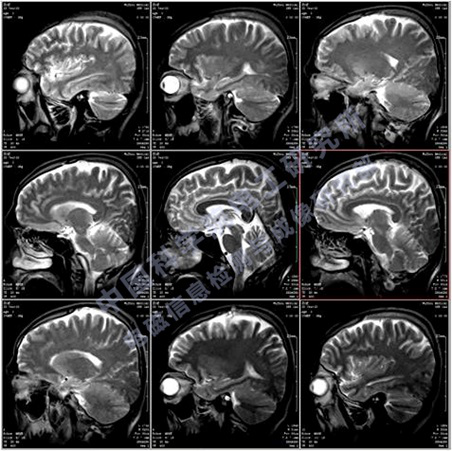

移動(dòng)式POCI磁共振成像儀屬于POCI(point of care imaging)成像裝備,也就是即時(shí)監(jiān)護(hù)成像,包括但不限于:神經(jīng)內(nèi)科和神經(jīng)外科的腦監(jiān)護(hù)成像、新生兒腦監(jiān)護(hù)、口腔醫(yī)學(xué)以及運(yùn)動(dòng)損傷監(jiān)護(hù)等,主要用于各類相關(guān)臨床醫(yī)院、科研機(jī)構(gòu)、研究型醫(yī)院,用于臨床診斷和疾病的動(dòng)物模型研究、認(rèn)知研究、新藥研發(fā)等。我們研發(fā)的移動(dòng)式POCI磁共振成像儀,采用了最新的輕量化永磁磁體技術(shù)和高效率的矩陣梯度技術(shù),使得整機(jī)具有更高的磁場強(qiáng)度、更低的使用成本、更好的成像效果和適用性。目前國內(nèi)MRI裝機(jī)量超過了11000臺(tái),而移動(dòng)式POCI磁共振成像儀目前國內(nèi)外還沒有成熟的產(chǎn)品。預(yù)計(jì)將來移動(dòng)式POCI磁共振成像儀的需求量接近全身MRI設(shè)備的需求,其總市場價(jià)值約有150億元,因此移動(dòng)式POCI磁共振成像儀具有良好的市場前景和經(jīng)濟(jì)效益。